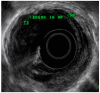

Gastric and esophageal tumors are diverse neoplasms that involve mucosal and submucosal tissue layers and include squamous cell carcinomas, adenocarcinomas, spindle cell neoplasms, neuroendocrine tumors, marginal B cell lymphomas, along with less common tumors. The worldwide burden of esophageal and gastric malignancies is significant, with esophageal and gastric cancer representing the ninth and fifth most common cancers, respectively. The approach to diagnosis and staging of these lesions is multimodal and includes a combination of gastrointestinal endoscopy, endoscopic ultrasound, and cross-sectional imaging. Likewise, therapy is multidisciplinary and combines therapeutic endoscopy, surgery, radiotherapy, and systemic chemotherapeutic tools. Future directions for diagnosis of esophageal and gastric malignancies are evolving rapidly and will involve advances in endoscopic and endosonographic techniques including tethered capsules, optical coherence tomography, along with targeted cytologic and serological analyses.